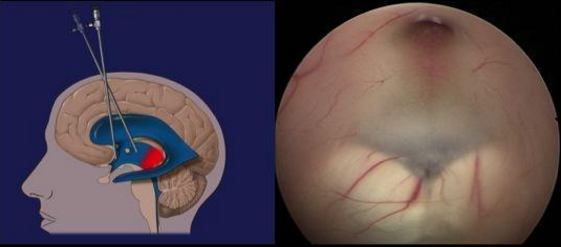

▲三脑室底造瘘术

在福建医科大学附属第一医院江常震教授的指导下,郭协力副院长、齐震主任、陈晓海副主任医师及蔡明发主治医师等人通力合作,于7月22日对王先生进行了微创神经内镜三脑室底造瘘术。手术利用脑室镜微创进入第三脑室,开放第三脑室底部约5mm,再造脑脊液循环通路,使脑室内积水得以流出。手术用时1个多小时就顺利完成,术后患者恢复到患病前状态,脑积水症状及影像均有不同程度的好转。